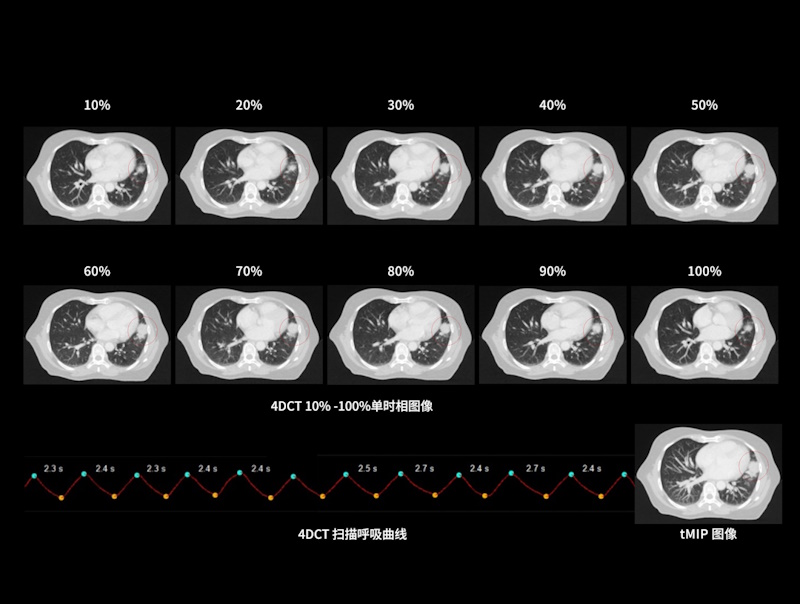

运动器官动态追踪

支持前瞻式断层扫描、前瞻式螺旋扫描和回顾式螺旋扫描,应对各类放疗应用场景

联影自研压力传感式呼吸门控系统精准记录规律呼吸、咳嗽异常等各类临床场景下的呼吸信号

基于实际呼吸频率情况自适应推荐最佳螺距参数,相较于传统固定螺距采集,有效减少图像运动伪影

超快机架转速结合球管超长连续曝光能力,采集范围相较传统大孔径CT系统提升2倍*,覆盖各类临床应用场景

*相较于0.5秒/360°转速、120秒球管最长曝光时间的CT系统